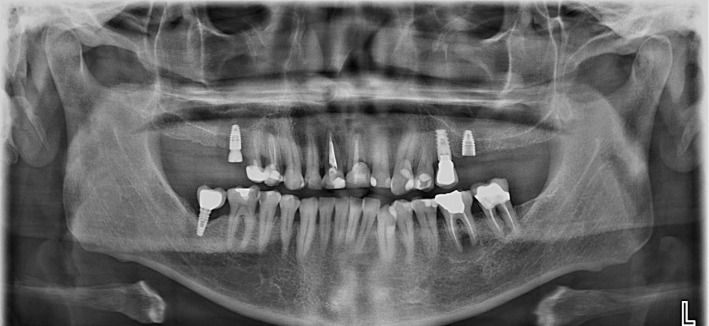

Diagnóstico por Imágenes

Contamos con un servicio integral de diagnóstico por imágenes para niños y adultos, lo que nos permite planificar y realizar tratamientos con la mayor precisión.

Ortopantomografía digital

Tomografía Cone Beam (3D)